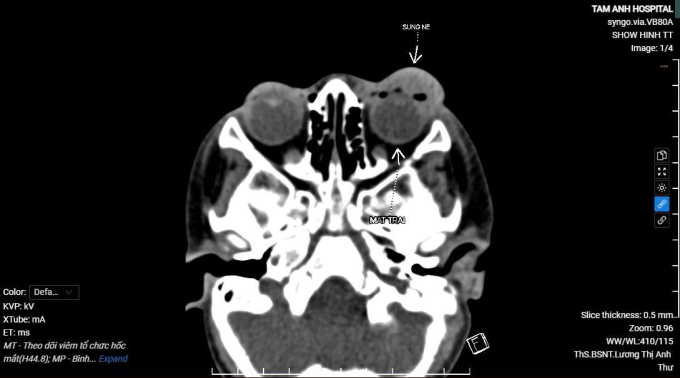

Với bé trai này, chụp CT đánh giá mức độ lan rộng và nguy cơ biến chứng ghi nhận nhãn cầu cân đối, tổn thương chưa ảnh hưởng tới hệ thống thần kinh thị giác hay các tổ chức sâu trong hốc mắt. Bé được bác sĩ khoa nhi và khoa mắt phối hợp điều trị, sử dụng kháng sinh đặc hiệu kết hợp chích dẫn lưu ổ mủ, sau 5 ngày mắt bớt sưng nề. Hai tuần sau, thị lực của bé trở lại bình thường.

Ảnh chụp CT hốc mắt của bệnh nhi. Ảnh: Bệnh viện Đa khoa Tâm Anh